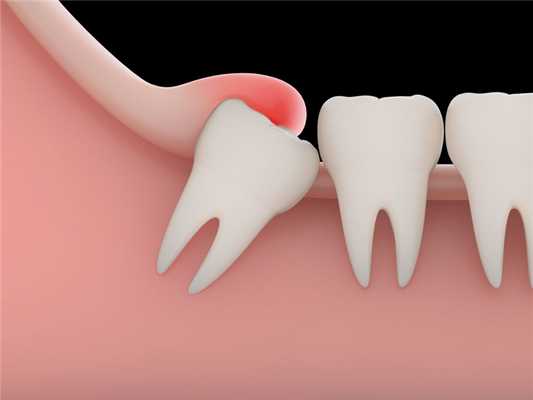

«Восьмерка» считается одним из самых проблемных зубов. Неудивительно, эти зубы появляются позже всех, места для них остается мало. Поэтому нередко зуб мудрости остается в челюсти не прорезываясь. Иногда «восьмерка» упирается в соседние зубы, щеки, растет под углом и причиняет множество неприятных ощущений.

Появление перикоронита связано с неправильным прорезыванием зубов. Есть несколько теорий развития данного нарушения. По одной из них, неправильное прорезывание зубов закладывается во время внутриутробного развития, когда формируется зубочелюстная система. Если ребёнок наследует от одного родителя небольшую челюсть, а от другого — крупные зубы, зачатки располагаются неправильно. При прорезывании таким зубам может не хватить места и они сместятся в сторону рядом стоящих зубов [3] .

Согласно другой теории, неправильное прорезывание зубов вызвано изменением зубочелюстной системы в процессе эволюции. Со временем ширина зубной дуги уменьшилась на 10 мм, однако количество зубов не изменилось [6] . В виду того, что зуб мудрости прорезается в последнюю очередь, ему часто не хватает места.

Зубы мудрости, как правило, прорезаются в 17-25 лет. Процесс их появления может затянуться на несколько недель или даже месяцев. При этом зуб не всегда прорезывается полностью: часть коронки остаётся под толстым слоем слизистой оболочки — капюшоном.

Чаще перикоронарит наблюдается в области прорезывающихся восьмерок или зубов мудрости. Это связано с тем, что они появляются уже во взрослом возрасте, тогда, когда зубной ряд сформирован, а челюсть перестала расти. В конце зубного ряда попросту не остается места для крупного зуба, в связи с чем восьмерка растет под наклоном или частично скрывается десной. Если зуб мудрости начинает прорезываться до 20 лет, обычно процесс протекает легко. В старшем возрасте процесс чаще осложняется перикоронаритом.

Ретинированные и дистопированные зубы, а также ситуации, при которых полное прорезывание зуба неизбежно повлечет за собой нарушения прикуса или смещение соседних зубов, — это показания к хирургическому лечению другого плана. Врач может предложить удаление зуба, а в случаях заболевания над «восьмеркой» это почти всегда единственный вариант решения проблемы.

Дело в том, что зубы мудрости не несут функциональной нагрузки, очень часто прорезываются под наклоном, мешают соседним зубам и повышают риск осложнений, в том числе дефектов прикуса. Поэтому целесообразным считается удаление «восьмерки» и дальнейшие мероприятия по устранению воспаления в мягких тканях.